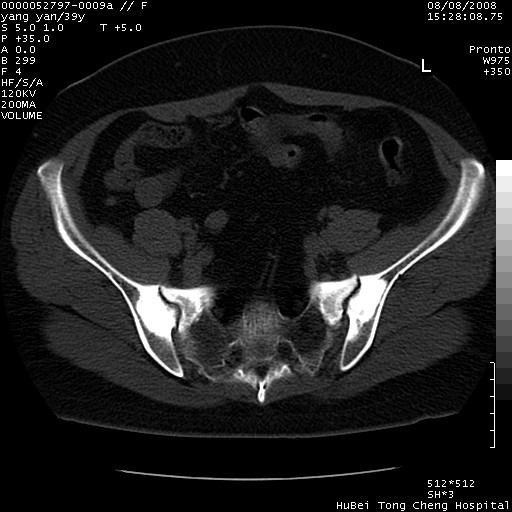

患者 女,39岁。因外伤检查,偶然发现。

典型!双侧骶髂关节致密性骨炎。

典型!病变主要累及双侧髂骨。常见于育龄期妇女。

致密性骨炎,一般不跨越关节面,可是这个骶骨关节面也有硬化。

髂骨致密性骨炎系一种以骨质硬化为特点的非特异性炎症,有高度致密的骨硬化现象,尤其以髂骨下2/3更为明显,但关节间隙则无改变。因位于骶髂关节,且该关节症状明显,故又称之为“骶髂关节致密性骨炎”。 本病90%以上为中年女性,以妊娠后期、尤其分娩后为多见,亦可见于尿路或女性附件慢性感染后,或盆腔内其他感染。此外,臀骶部的外伤亦可诱发或引起本病。  妊娠、分娩及外伤均可引起骶髂关节韧带的撕裂而易使局部的血供受阻。因此早期局部呈现充血、水肿及渗出增加等,渐而局部出现增生与变性反应,随着胶原纤维的致密化而向硬化演变;血管形成厚壁血管,易闭塞而引起髂骨耳状面处缺血和缺氧,骨质呈现硬化性改变,以致手术时局部出血较少。骶髂关节囊壁显示纤维增生、弹性降低及松动样改变。继发于盆腔内炎症者亦出现相类似的病理改变,可能系细菌内毒素作用所致。